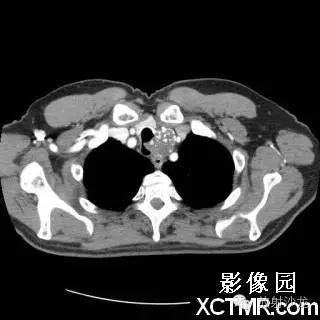

On the contrast-enhanced CT of the chest, there is a heterogeneous mass arising from the left lateral wall of the trachea. The mass demonstrates extratracheal extension as well as extension into the tracheal lumen. (Figure 1 and Figure 2). The mass also contains internal calcifications (arrows), representing chondroid matrix mineralization (Figure 3 and Figure 4).

胸部增强扫描示气管左侧壁发出一不均质的肿块影,肿块向气管内外扩展(图1、2)。其内可见钙化影(箭头),代表软骨基质的钙化(图3、4)。